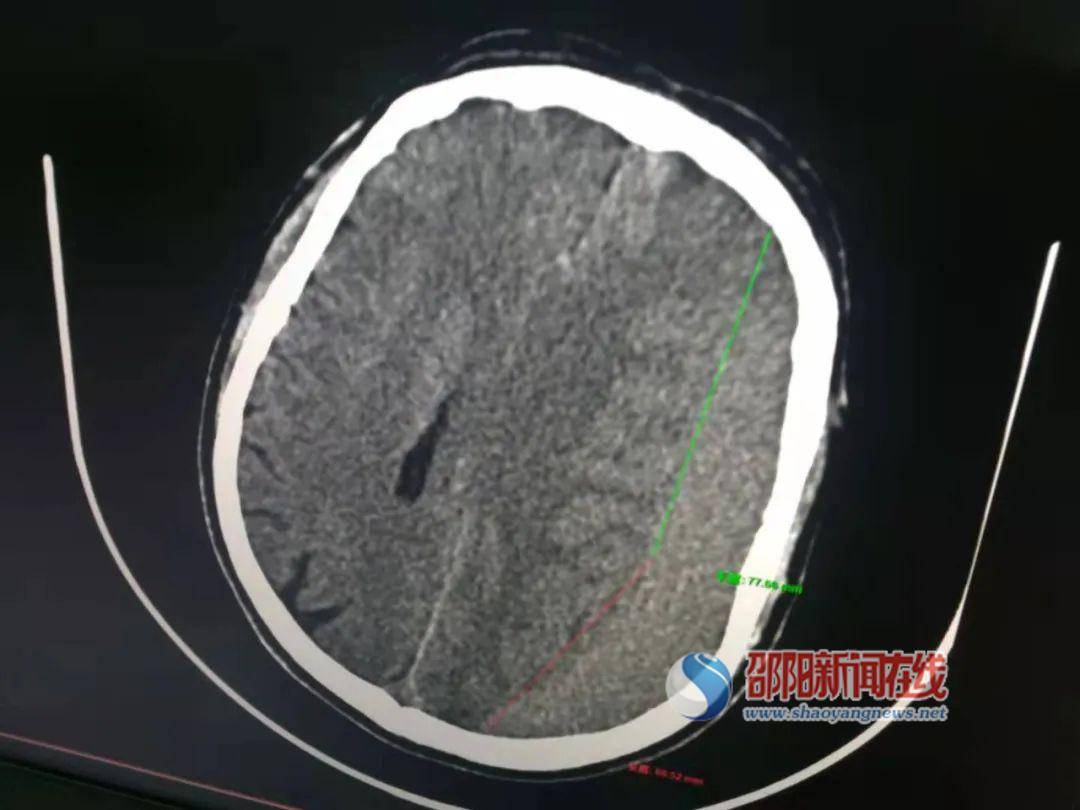

术前图片

以收治的两例患者来看疗效 , 患者 , 刘某某 , 男 , 56岁 , 聋哑人 , 入院初步诊断:右侧慢性硬膜下血肿并左侧肢体不全瘫 , 手术指针明确 , 原方案拟普通钻孔引流 , 全麻后 , 做一6cm切口 , 开颅电钻钻一骨孔 , 然后冲洗至液体清亮后留置软管 , 新方案床旁直接置入硬通道 , 结合注射尿激酶溶血 , 3天后血肿基本清除 , 患者康复步行出院 。